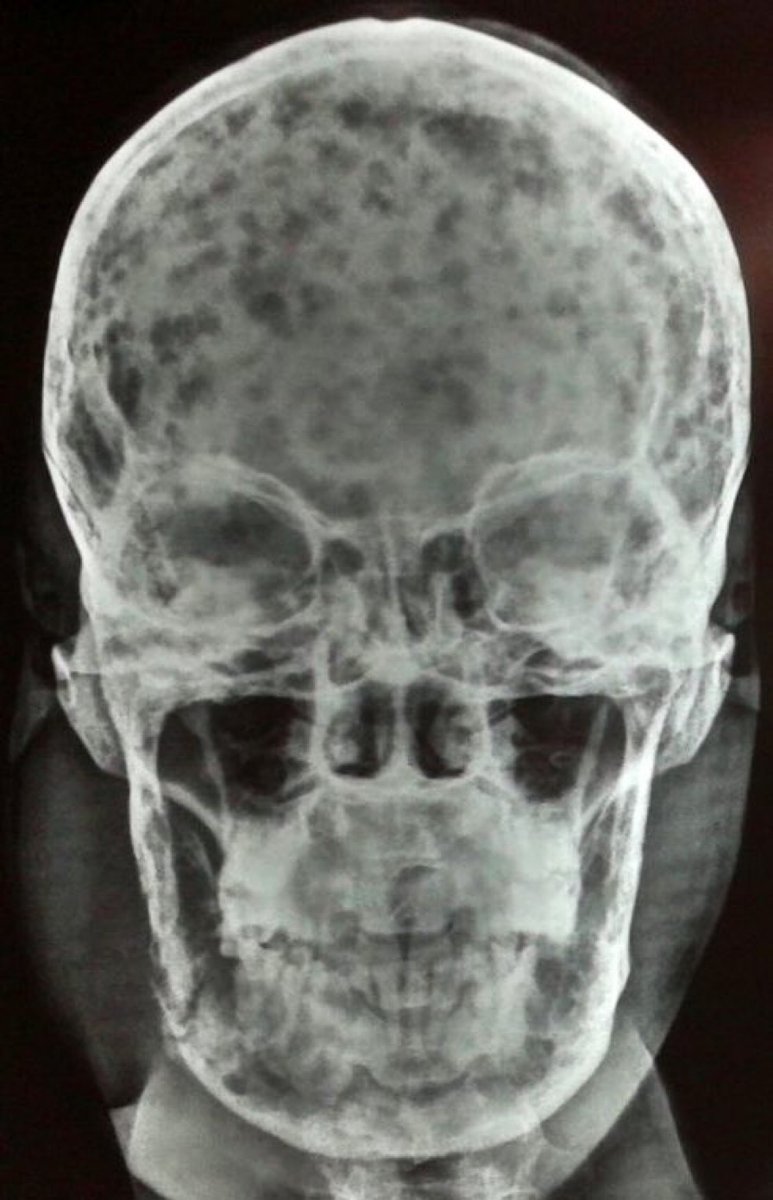

A 46-year-old man presented with shortness of breath, low back pain & weight loss. Labs w/⬇️Hb, ⬆️Ca. What is the diagnosis? #Medtwitter #Hemetwitter #MedEd tinyurl.com/39rvkcuj